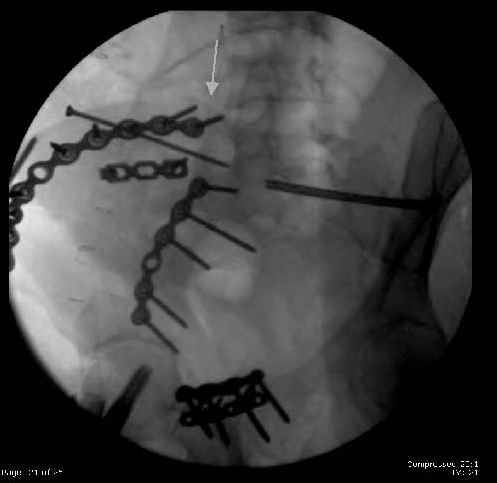

Here are the postop fluoros.

First exposed symphysis & clamped w/Faraboeuf as close to anatomic as possible.

Then extended to R ilioinguinal,really just the lateral window.

Reduced the triangular wedge piece of iliac wing to posterior intact ilium (crescent), held w/k-wire, then used 3-hole push plate to keep from moving, lagged from lat-med w 3.5 screw.

Then 6-hole plate along brim with 1 screw in R sacral ala. Then lagged 2 screws along crest A --> P. finally 10-hole plate along inner aspect of crest. R posterior ilium still a bit stepped off.

Symphysis then 'fine-tuned' & reduced as close as possible to anatomic (but, still with forward rotation of R hemipelvis - or, is it extension?) Accepted that amount of deformity and plated symph

with 4-hole symphyseal plate.

Fluoroed L SI joint and it seemed stable, but wide. So, applied c-clamp to try to squeeze down L SI joint (and note, on the last slide attached, that it's still wide), and got it closer. Single perc Iliosacral screw 40mm thread.

Applied second plate anteriorly on symphysis as I wasn't confident L SI was as stable as it could be and wanted to protect it better.

Thoughts? Thanks for the advice, it's appreciated.

The mal-alignment that you indicated by the arrow in your photo of the ilium, do you have some idea as to how that occurred? was the crescent component locked in such a manner that it could not be moved?